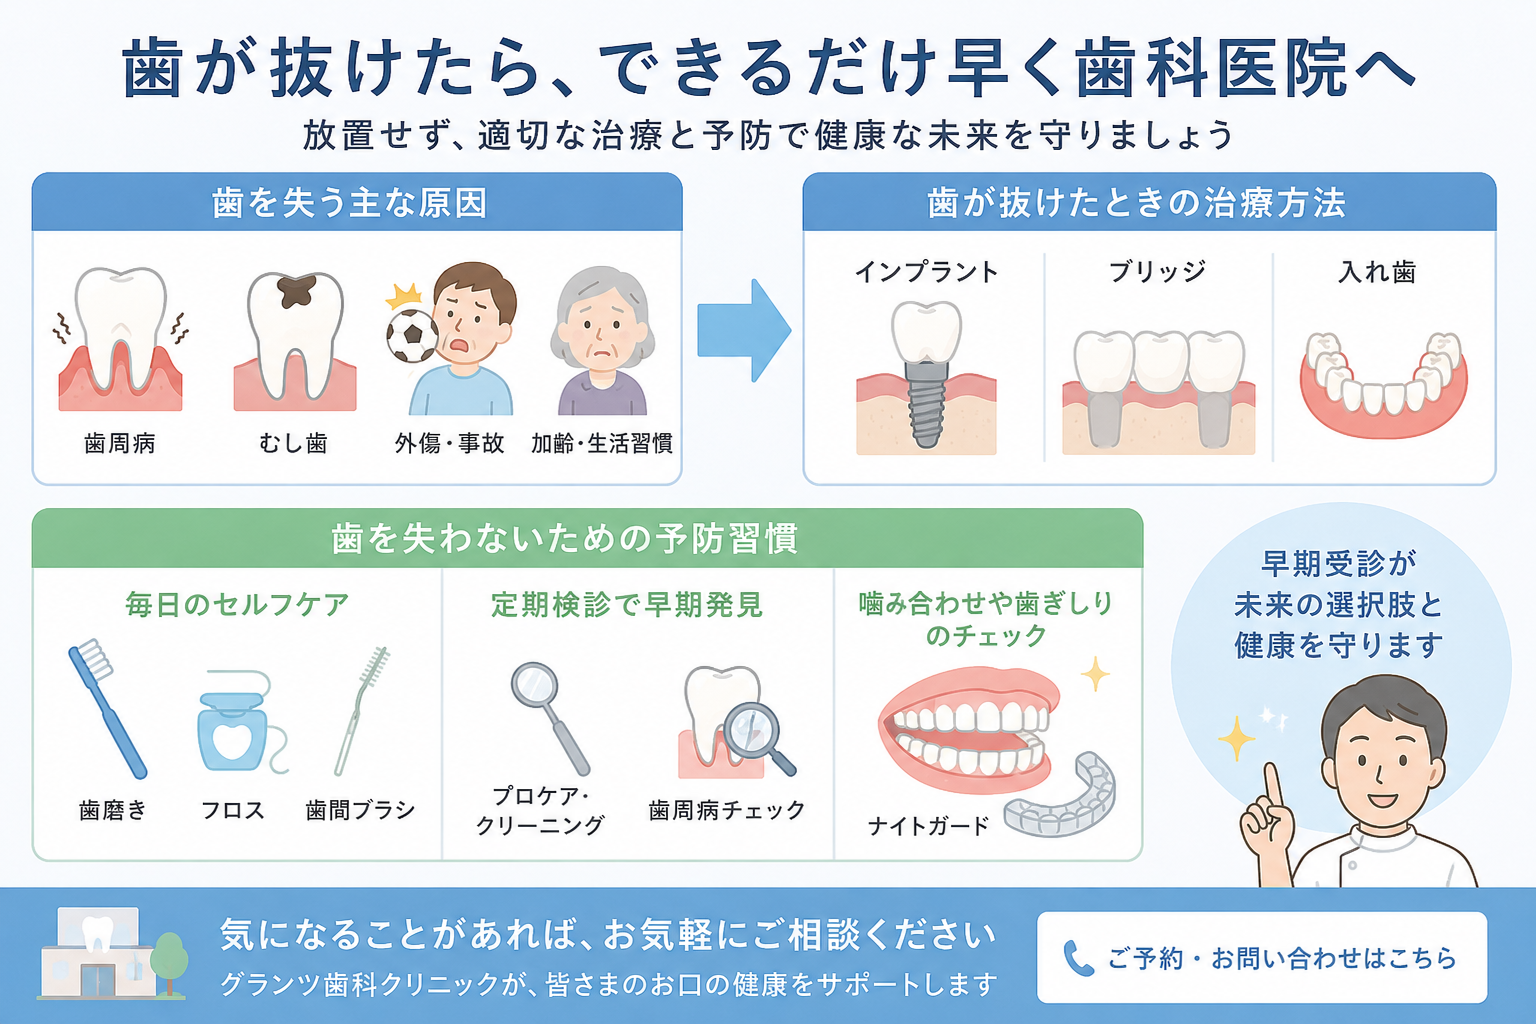

この不正咬合をそのままにしておくと、

- 食べ物がよく噛めない

- むし歯になりやすい

- 歯周病になりやすい

- 口が閉じにくい為、口腔乾燥により口臭の原因になる

- アゴの関節に負担をかける(顎関節症)

- 歯が割れたり折れたりしやすい

などの問題がでてきます。

姫路駅前グランツ歯科では、

来院される患者様が、安心・満足以上の[心地よさ]や[感動]される治療を提供出来る様に、日頃から知識や技術のスキルアップに力を入れております。まだまだ至らない点もございますが、スタッフ一同、心を込めて対応させていただきます。これからもどうぞ宜しくお願い致します🙇♀️✨

見た目や噛み合わせでお悩みの方、お一人で悩まず、まずはご相談にいらしてみてください。

解決策や、あなたの人生にプラスとなる新しい発見があるかもしれません😌💡

ご予約は、ホームページからのネット予約(初診の方のみ)か、お電話 ☎︎ 0792218241 にて承ります。